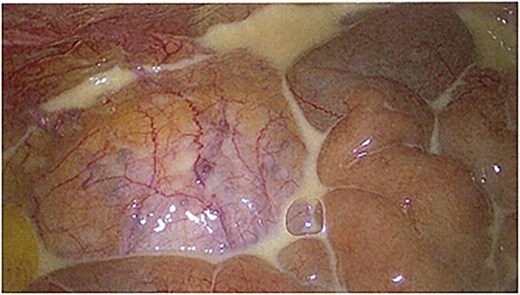

On day 4 of admission, she progressed to theatre for a laparoscopic cholecystectomy. On entry to the abdominal cavity, milky/purulent fluid appeared in all four quadrants (Fig. 1). A diagnostic laparoscopy was performed to try to identify the cause of this. Her pelvic organs, caecum, transverse, and sigmoid colon were unremarkable. The small bowel was examined in its entirety, revealing no abnormality. The stomach and duodenum were inspected and were normal. There was saponification of the fat overlying the pancreas, and adhesions were present from the liver to the abdominal wall. The gallbladder was thin-walled (Fig. 2). No alternative source of peritonitis was identified; therefore, the decision was made to proceed with the cholecystectomy, which was uncomplicated. A 15 French Blake drain was placed in the pelvis.

Laparoscopic image showing chyle found on entry to the peritoneal cavity.